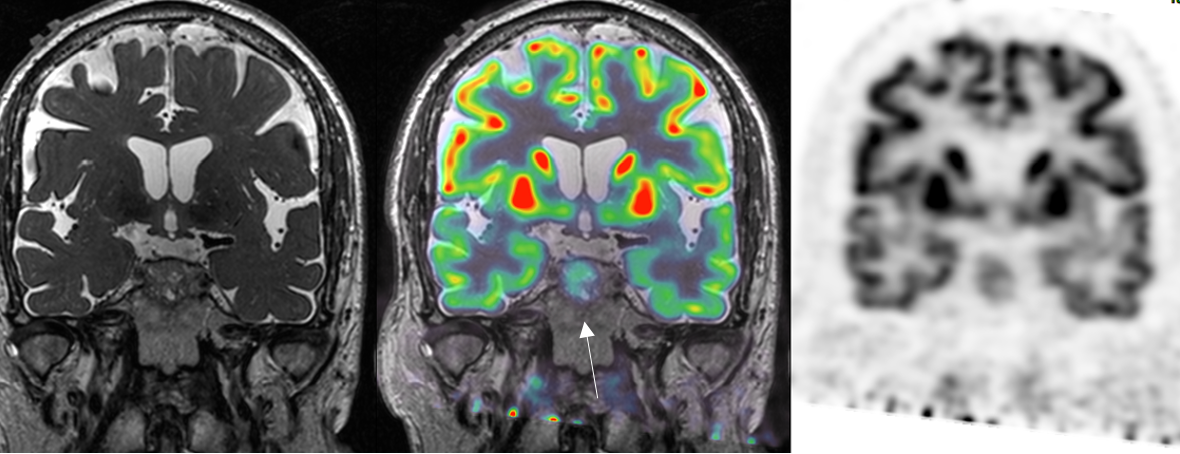

Figure 3

Coronal PET‑CT F18‑FDG with MRI coregistration: moderate uptake of infiltrative sellar lesion. Moderate FDG uptake of infiltrative sellar lesion.